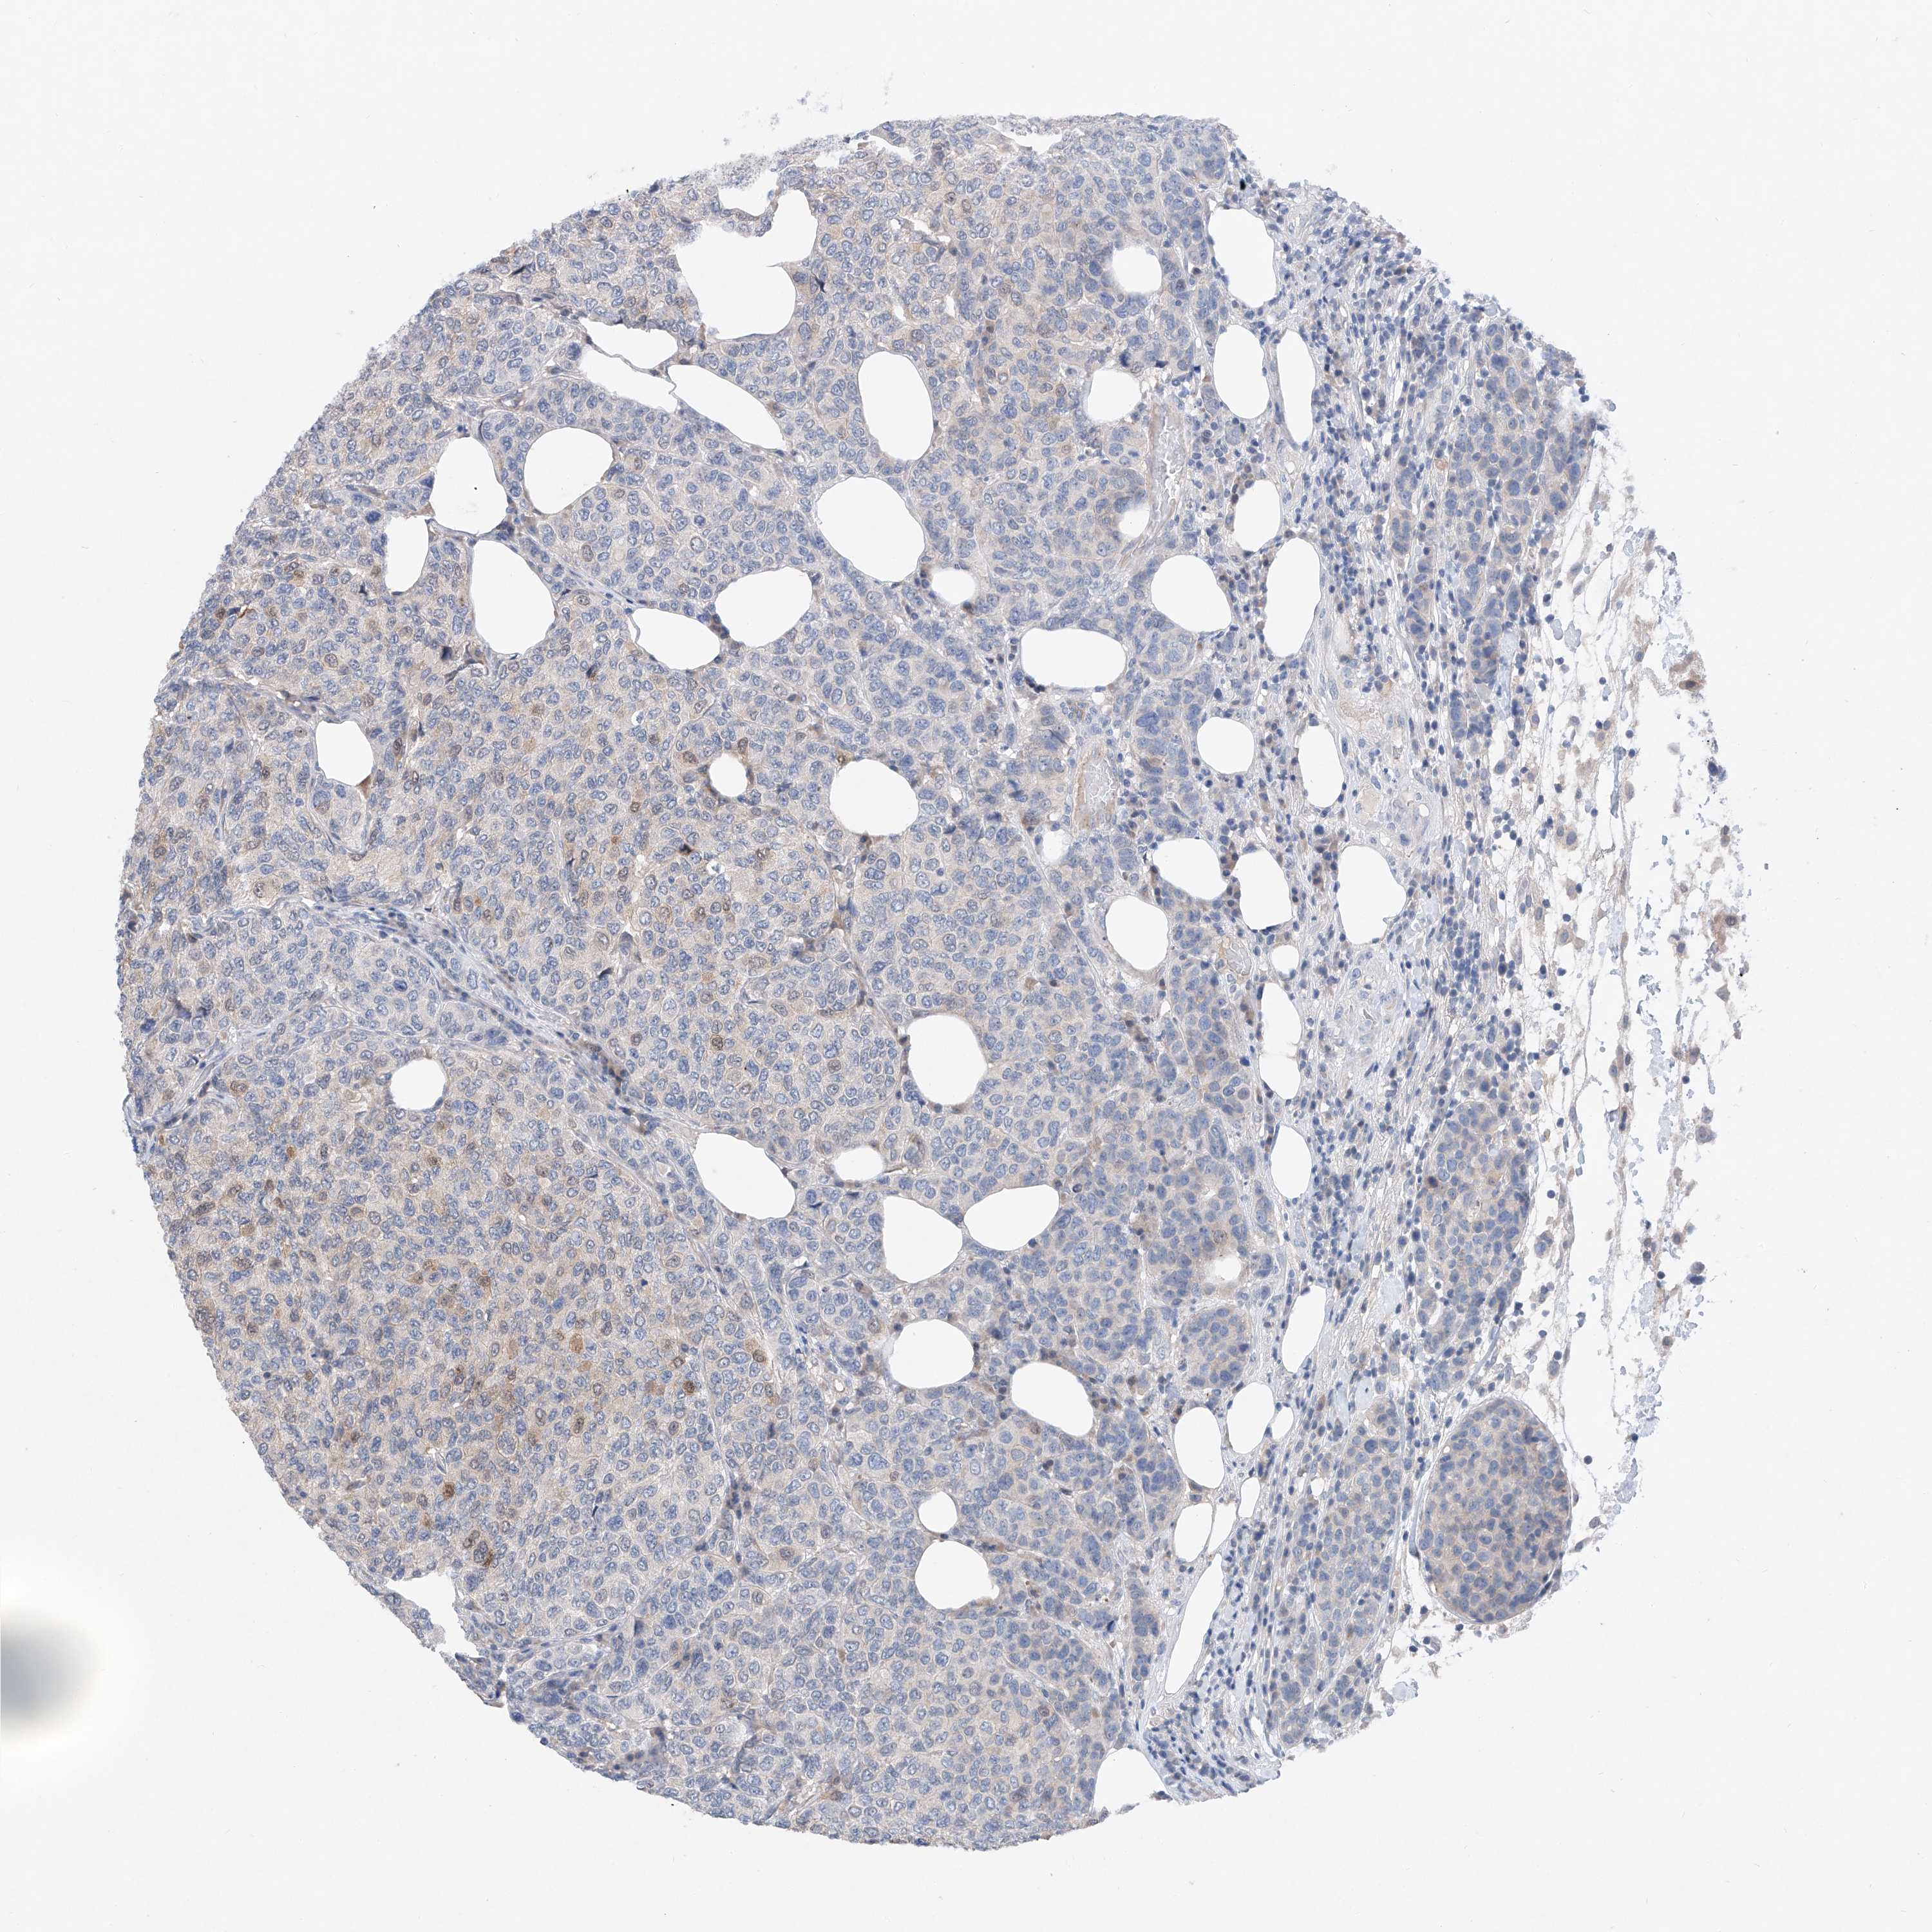

BRCA TCGA BRCA VALIDATION PROTEIN EXPRESSION

ANTIBODIES

AND

VALIDATION